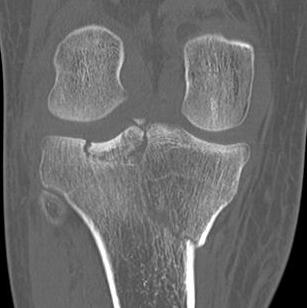

VI. Bi-condylar + metaphyseal fracture

- fracture separating metaphysis from diaphysis

- highest incidence of vascular injury